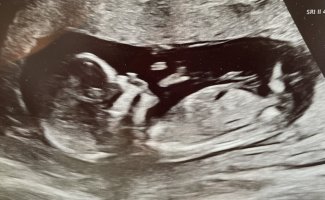

Gutt?!

Spennende altså. Tror vi må få vite kjønn på ordinær UL for jeg klarer antageligvis ikke å vente, haha.Gutt?!

Men så ble jeg litt usikker med en gang jeg postet. Kanskje den er mer rett? Isåfall jente!Spennende altså. Tror vi må få vite kjønn på ordinær UL for jeg klarer antageligvis ikke å vente, haha.

Ja, jeg synes kanskje den er mer rett. Har sittet og studert videoklippet flere ganger nå og tenker den er mer i linje med ryggraden enn oppover. Kjempespennende uansett!Men så ble jeg litt usikker med en gang jeg postet. Kanskje den er mer rett? Isåfall jente!

Nub'en pekte ned i uke 12.